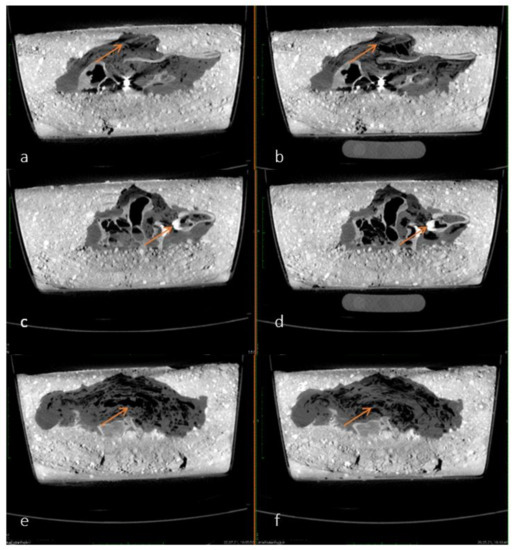

On the exemplified radiographs in Figure 5a–d, a darkening can be seen covering the pig’s head and paw and progressing over time. This could be an indirect sign of decomposition of the soft tissues. The outline and the projectile in the eye socket of the pig are clearly visible in each image. The projectile can be seen in black due to the high combined density of the metal and the surrounding concrete.

Figure 5.

(a–d) Comparisons of X-ray images from 30 September 2020 (a), 21 December 2020 (b), 3 March 2021 (c) and 25 August 2021 (d). The darkening is shown by arrows. The projectile is marked with a circle in all four images. Quality of the images is due to the reduced radiation density in the portable X-ray machine.